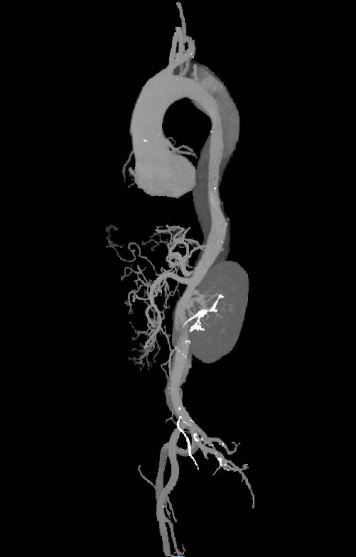

【术后复查主动脉CTA】(2025-04-30)

对比2025-1-7检查结果:

1. 主动脉夹层支架置入、双侧颈总动脉-锁骨下动脉搭桥术后,支架周围及吻合口未见明确渗漏征象;降右主动脉至右颈总、外动脉仍见夹层,较前相仿,请结合临床。

2. 主动脉窦增宽,同前。

3. 主动脉及冠状动脉粥样硬化。

4. 右椎动脉显示不清,请结合临床。

5. 心包少量积液,较前减少。

6. 双肺散在炎症,较前减少;左上肺下活段支气管扩张,较前相仿。

7. 双肺结节,考虑炎性结节可能,大致同前,建议定期复查。

8. 双肾小结石。(图5、图6)

图5 患者2025-04-30复查主动脉全层CTA

图6 2025-04-30患者术后主动脉全程CTA图像